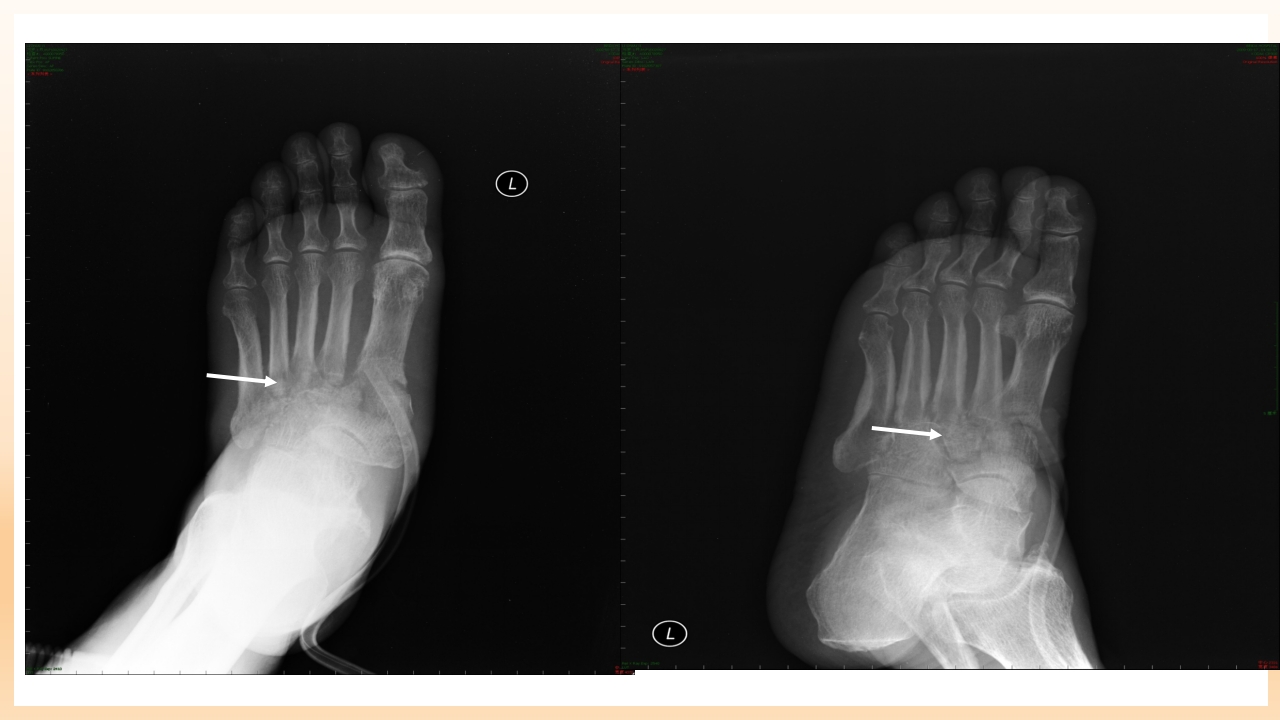

糖尿病足的治疗与护理 目录/content 一 糖尿病足的定义 二 糖尿病足发病机制及诊断? 三 糖尿病足如何治疗? 四 如何预防和护理糖尿尿足? 1 糖尿病足的定义 糖尿病足定义 糖尿病足:主要是与糖尿病下肢远端神经异常和不同程度的外 周血管病变相关的足部感染、溃疡和(或)深层组织破坏。 由于神经营养不良和外伤的共同作用,可引起Charot关节。 是糖尿病最严重的和治疗费用最高的慢性并发症之一。 糖尿病足流行病学资料 国外资料显示: 在所有因糖尿病住院的有关问题中,糖尿病足占到47%。 5%-10%糖尿病患者有不同程度足溃疡,1%的糖尿病患者截 肢。 糖尿病足是许多国家截肢首位原因。 中国糖尿病防治指南,2005,55 糖尿病足流行病学资料 在我国糖尿病足患病率占糖尿病患者的14%, ...